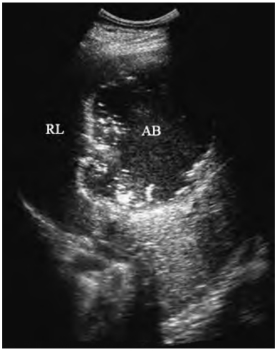

图23-14 肝脓肿声像图

脓肿(AB)内部脓汁稠厚,并有坏死肝组织碎片的斑状强回声

②脓汁稠厚:无回声区内有密集细小点状低回声,有坏死肝组织碎片时可见斑状强回声,具有随呼吸运动和体位改变而浮动的特征(图23-14)。